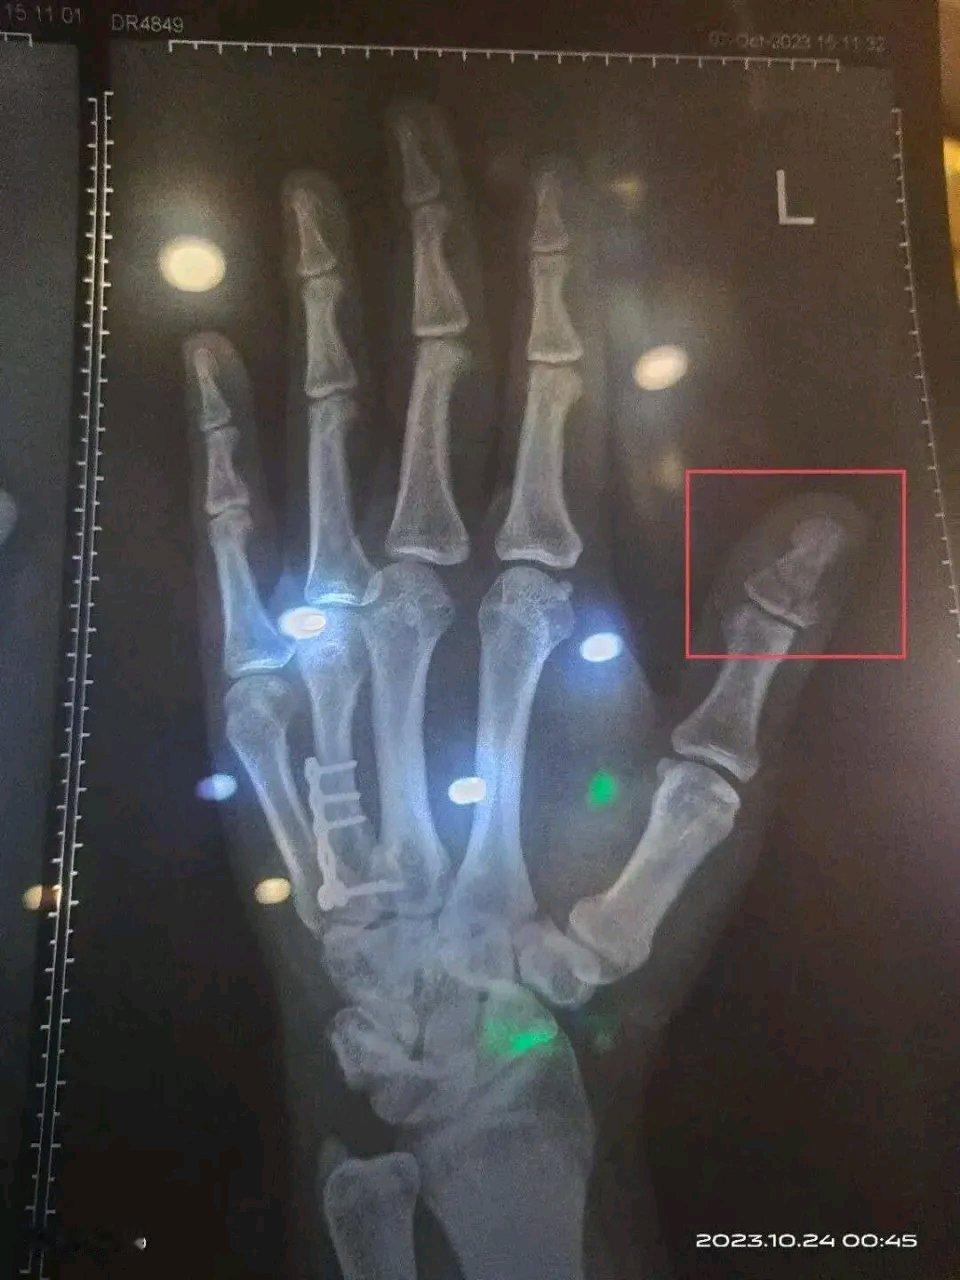

外卖骑手工伤维权太难了!30岁的杜北送外卖第39天,在过喷水斑马线时侧滑摔倒,左手大拇指粉碎性骨折。第二天,他的骑手账号就被站长删了,从此开启漫长维权路,遭遇多方“踢皮球”和疑似诈骗。661天后,仲裁委裁定118221元工伤赔偿,可企业又起诉把案子拖入法庭。 还有外卖骑手刘某,因路面湿滑摔伤被认定十级伤残,公司虽代扣社保但费用全让他承担,还不支付工伤待遇,拒绝派单。这些例子都显示,“腾飞的共享经济”让外卖骑手成了劳动保障体系外的“耗材”。不过像杜北说的,有理就一层一层找,总会有解决办法。